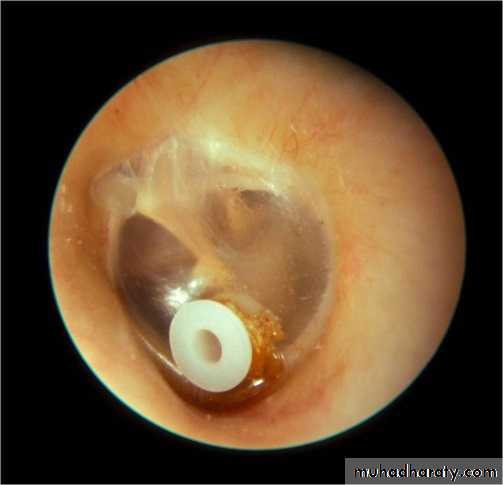

Surgery should only be recommended for diseases persistent more than 3 months. The surgical treatment consists of myringotomy, aspiration of thick mucoid material and the insertion of a grommet. This grommet provides adequate ventilation of the middle ear and is essentially an artificial ET. After several months however, the grommet is slowly extruded.

Otitis media with effusion Grommet

Grommet in place